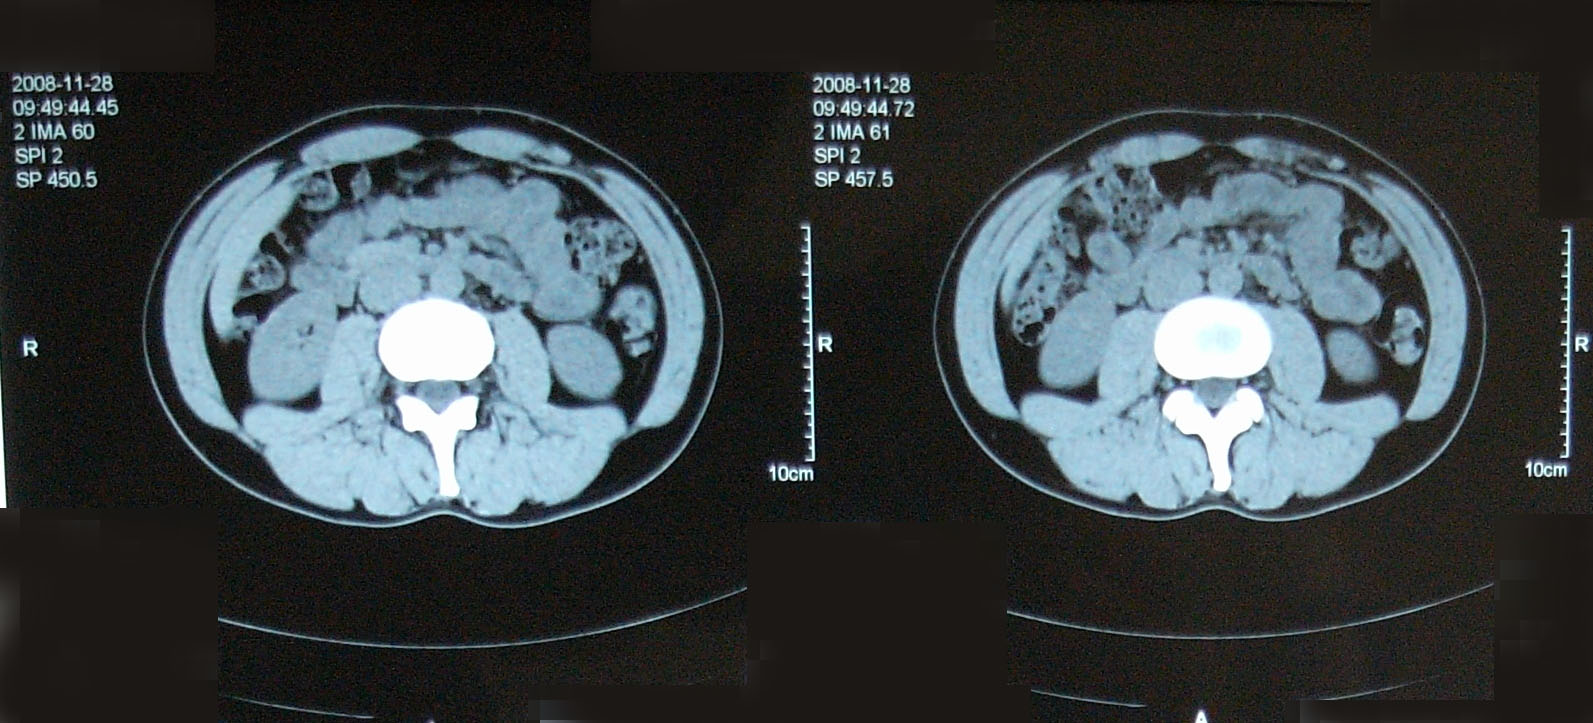

問題なし 【腫瘍マーカー】 HCGβ:<0.1 問題なし 【中性脂肪】 219→137 基準内(38-193)に入った 今回、検査画像をデータでもらってきた。 後腹膜の転移した箇所の前後4枚を2003年から2010年まで並べてみた。 http://gomatsushita.gozaru.jp/ct/album/index.html 2006/7/18の画像を見ると腫瘍がハッキリ見える。 BEP2クール後の9/27の画像では明らかに縮小もしくは消滅。

勘違いしてた・・・ なので単純CT。 横になって撮るだけなので非常に楽ですね。その分撮影される画像も解像度が低くなりますが・・・ しかし、思えば2005年末頃の単純CTからリンパ転移が疑われ始め、その次からはずっと造影剤を使用したCTだったわけだ。 2008年末の今、やっとそこへ戻ってきたという感じがした。 検査後の帰り、病院の最寄り駅のパン屋で朝食。 改札横に店があるのでガラス越しに行き交う多くの人を眺めながら思う。 2006年の入院中、ヨメも色々思いながらここを通ったんだろう、と。 何ヶ月も。 暑い日も雨の日も。 ただただ「感謝」あるのみです。 本日の検査結果は12/8。

BEP治療をして退院後2年が経ちました。

やっと2年かぁ。 次の1年はどうかな? 2009年の11月が楽しみだ。